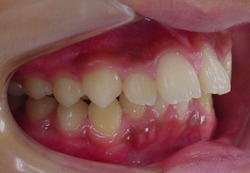

初診時

終了時